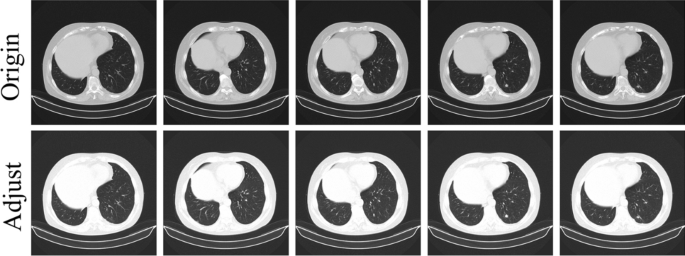

The lung cancer images of patients in the LUNA16 dataset are computed tomography (CT) images. CT imaging involves scanning a specific thickness of a cross-section of the human body using precisely directed X-rays. Based on the received X-ray signals, a 3D image of the body section is reconstructed, providing a higher spatial resolution and clear three-dimensional lesion images compared to X-rays. The LUNA16 dataset includes several CT images containing lung nodules. The information stored in the original CT files obtained through computed tomography includes images of all organs within the scanned area of the body (including interference areas such as air and blood vessels). To enhance the segmentation of lung nodules by the model, following29, we first perform windowing on the CT images to highlight the lung area. Several CT images from the LUNA16 dataset, before and after windowing, are shown in Fig. 4. Subsequently, we use a linear interpolation algorithm to resample the CT images in the LUNA16 dataset, ensuring that the spacing between various scan planes for each patient’s CT image is 1mm. This is done to address the issue of inconsistent spatial scales among scan planes caused by different scan plane spacings in CT images (Fig. 5).